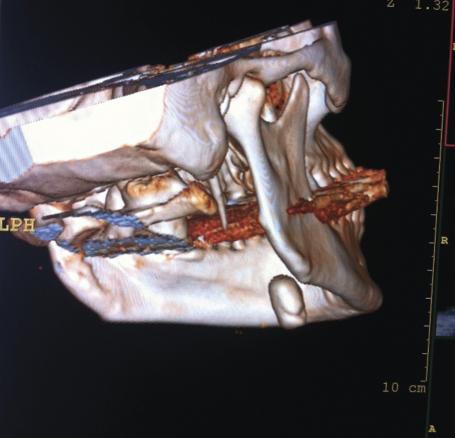

L’examen biologique est normal : absence de syndrome inflammatoire, hémogramme sans anomalie. La tomodensitométrie cervicale (fig. 2 et 3 ) montre une volumineuse formation calcifiée (20 × 15 mm). Cette masse correspond à la glande salivaire sous-mandibulaire droite totalement calcifiée, sans caractéristiques péjoratives.

L’examen biologique est normal : absence de syndrome inflammatoire, hémogramme sans anomalie. La tomodensitométrie cervicale (